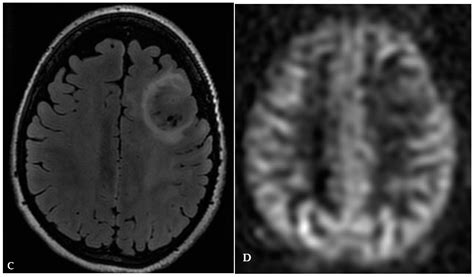

When a radiologist reviews brain imaging, they look for areas that show different signal intensities than the surrounding, healthy brain matter. These differences can be caused by various underlying processes, ranging from inflammation and infection to vascular issues or tumors. Because the causes are so diverse, it is impossible to determine the nature of a lesion based solely on its appearance on a scan; further investigation is almost always required.

• Neoplasms: Both benign (non-cancerous) and malignant (cancerous) tumors can appear as lesions.

Typically, the first step is an MRI with and without contrast. The contrast dye helps radiologists distinguish between different types of tissue and can highlight active inflammation or tumor blood supply. Blood tests may also be ordered to rule out systemic autoimmune diseases, infections, or metabolic issues.

• Follow-up Imaging: A scan performed a few months later to see if the lesion has grown, shrunk, or remained stable.

• Biopsy: In rare cases where a tumor is suspected, a surgical procedure may be required to obtain a tissue sample for laboratory analysis.